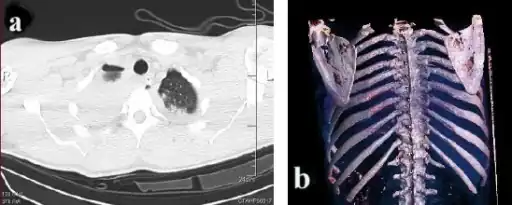

a)Axial computed tomography showing- bilateral scapular fractures (bilateral pulmonary contusion, left haemothorax) b) 3D computed tomography reconstruction shows bilateral scapular body fractures